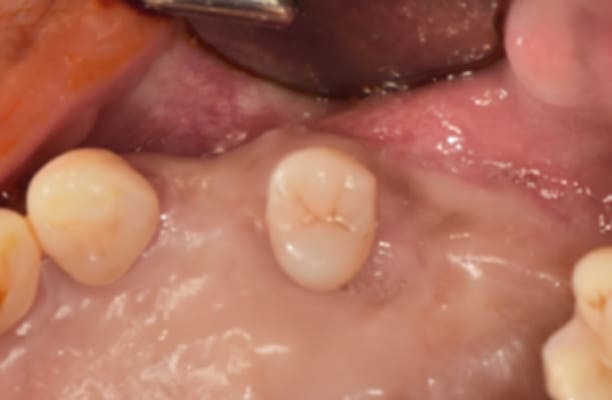

临床案例

-

术前 -

术后